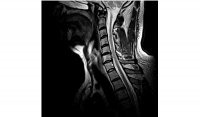

How bad is that? Is that a pinched cord I'm lookin' at?I didn't stay at Holiday Inn Express so I am going to leave this up to the Dr's......

It looks like there is some pressure on the cord at C-5. A fractured vertebra? It probably hurts, but I don't think it'll need surgery.I didn't stay at Holiday Inn Express so I am going to leave this up to the Dr's......

So far the consensus. My Chiropractor and the Technician. Will see the neurosurgeon shortly.It looks like there is some pressure on the cord at C-5. A fractured vertebra? It probably hurts, but I don't think it'll need surgery.